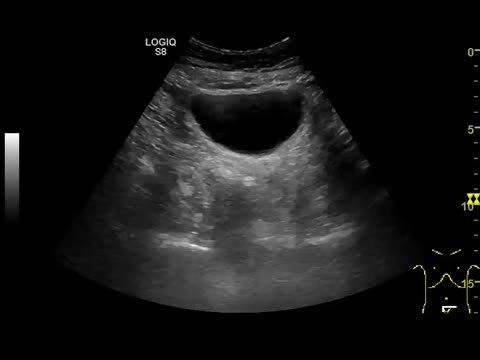

Ecográficamente las visualizamos como lesiones anecogénicas, redondeadas, de tamaño variable, de paredes finas y lisas, con refuerzo acústico posterior y sin contenido en su interior ni tabiques. Pueden ser corticales si dependen de la corteza renal o sinusales si se localizan en la zona medular10. Existen casos excepcionales en los que el quiste puede tener algún tabique en su interior, de mayor o menor grosor, con o sin contenido en su interior. Es en estas situaciones en las que hablamos de quistes complejos y es importante realizar una TAC para la correcta clasificación del quiste en la conocida como clasificación de Bosniak, que realmente es una clasificación radiológica de la TAC, no es una clasificación ecográfica (fig. 1 y video 1).

Imagen de la izquierda: Corte longitudinal y transversal en hipocondrio derecho. Quiste simple cortical de paredes finas, sin contenido, de unos 7cm. Imagen de la derecha: Corte longitudinal y transversal en hipocondrio derecho. Quiste cortical de paredes finas, con algún tabique fino en su interior.